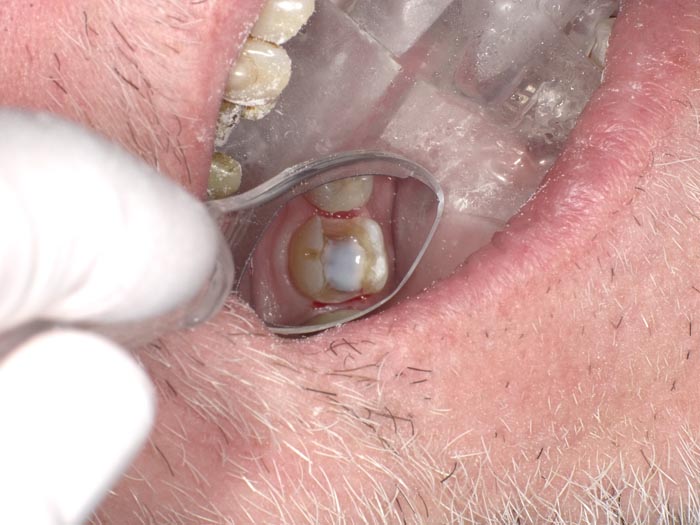

A 37-year-old patient presented for treatment after years of neglect. After administering anesthetic and placing an Isolite isolation device, we prepared teeth #10–12 and restored them

with Activa Bioactive-Restorative composite.

• Figure 1